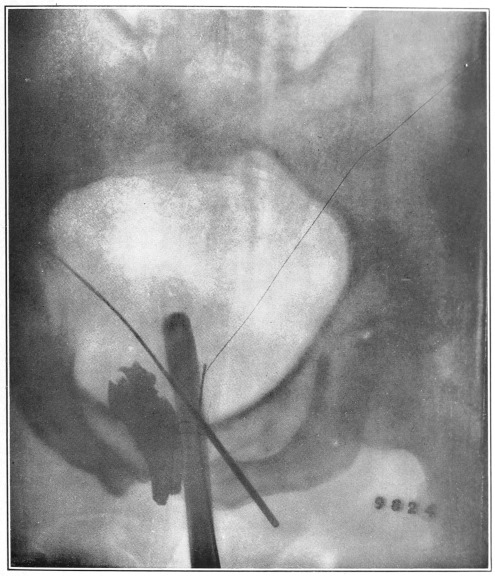

Nine Radiograph Illustrations Showing Mucus Channels and Cavities200

Fig. 4.

1, The dotted lines indicate the normal direction of the anus and rectum; 2, 4, the cavities or pouch formed by dilatation or ballooning from the storage of impacted feces; 3, a probe bent at right angles, and introduced through a speculum, to ascertain the depth of the pouch, which is frequently found to be two and a half inches.